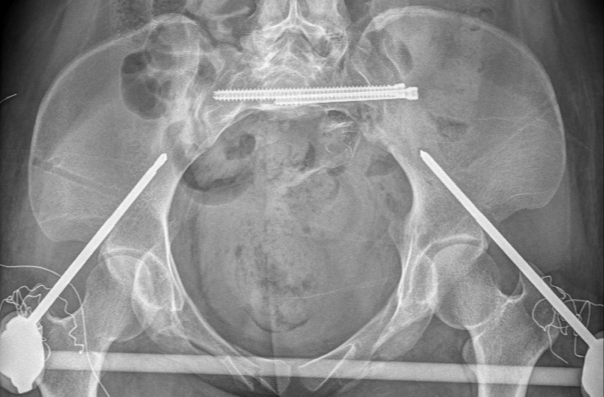

图五:术中透视验证复位结果

最后,手术团队利用智能化骨科手术机器人进行了螺钉通道及置入规划,并借助手持导向器,在实时动态三维可视化导航下,精准完成螺钉置入,完成了对该例骨盆骨折的微创治疗。

图六:螺钉置入规划、置入

术中透视验证螺钉置入效果

经过2个半小时的“数智化微创手术”,患者手术切口仅有5个,切口平均长度小于1cm,术中出血量仅有50cc,“真·微创”治疗效果着实令人满意。智能化骨科手术机器人真正实现了看得见的‘快准稳’,不仅让医生有了‘超级助手’,真正意义上实现骨盆骨折微创治疗,同时对患者康复和术后生活质量极为有利。

图七:患者术后三天影像资料